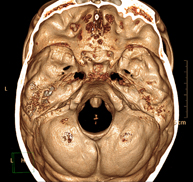

- Neurorradiología- TC Cráneo Prueba radiológica que consiste en obtener imágenes del cráneo de alta definición anatómica (tronco cerebral, cerebelo, cerebro, calota craneal, etc.), mediante el empleo de un equipo de TC (Tomografía Computarizada).Indicaciones: traumatismos, cefalea, trastornos de la memoria, pérdida de fuerza súbita en una extremidad o mitad del cuerpo. Prueba radiológica que consiste en obtener imágenes del cráneo de alta definición anatómica (tronco cerebral, cerebelo, cerebro, calota craneal, etc.), mediante el empleo de un equipo de TC (Tomografía Computarizada).Indicaciones: traumatismos, cefalea, trastornos de la memoria, pérdida de fuerza súbita en una extremidad o mitad del cuerpo.

- Pediatria- TC de crani Prova radiològica que consisteix en obtenir imatges del crani d'alta definició anatòmica, mitjançant l'ús d'un equip de TC (Tomografia Computeritzada). Indicacions: cefalea, estudi de tumors, traumatisme cranial. Prova radiològica que consisteix en obtenir imatges del crani d'alta definició anatòmica, mitjançant l'ús d'un equip de TC (Tomografia Computeritzada). Indicacions: cefalea, estudi de tumors, traumatisme cranial.